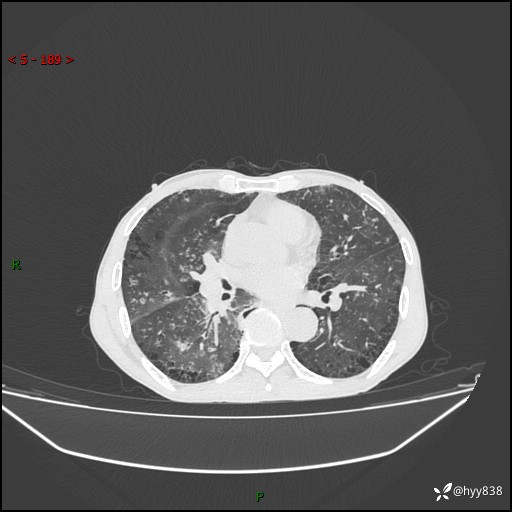

胸部CT平扫